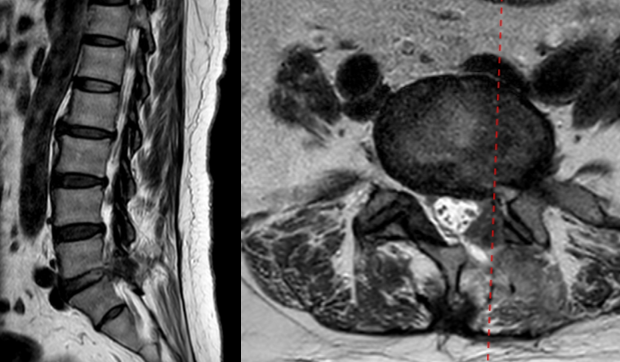

病例

女,51岁。

主诉:腰疼伴左下肢疼痛麻木4个月。

既往史:椎间孔镜下椎间盘切除术(L4-5)。

术前

术中:术中硬膜破裂,灌洗液压力30mmHg,硬膜破裂后1小时出现血压升高,心率加快,手术持续2小时。

术后:延迟苏醒,拔管困难,转ICU,6小时候拔管神志恢复正常。

术后

思考与建议:

警惕硬膜损伤

全麻下早期表现:血压升高,心率加快

尽快结束手术或中转开放手术

有条件情况下给予硬膜修补

多数患者预后良好